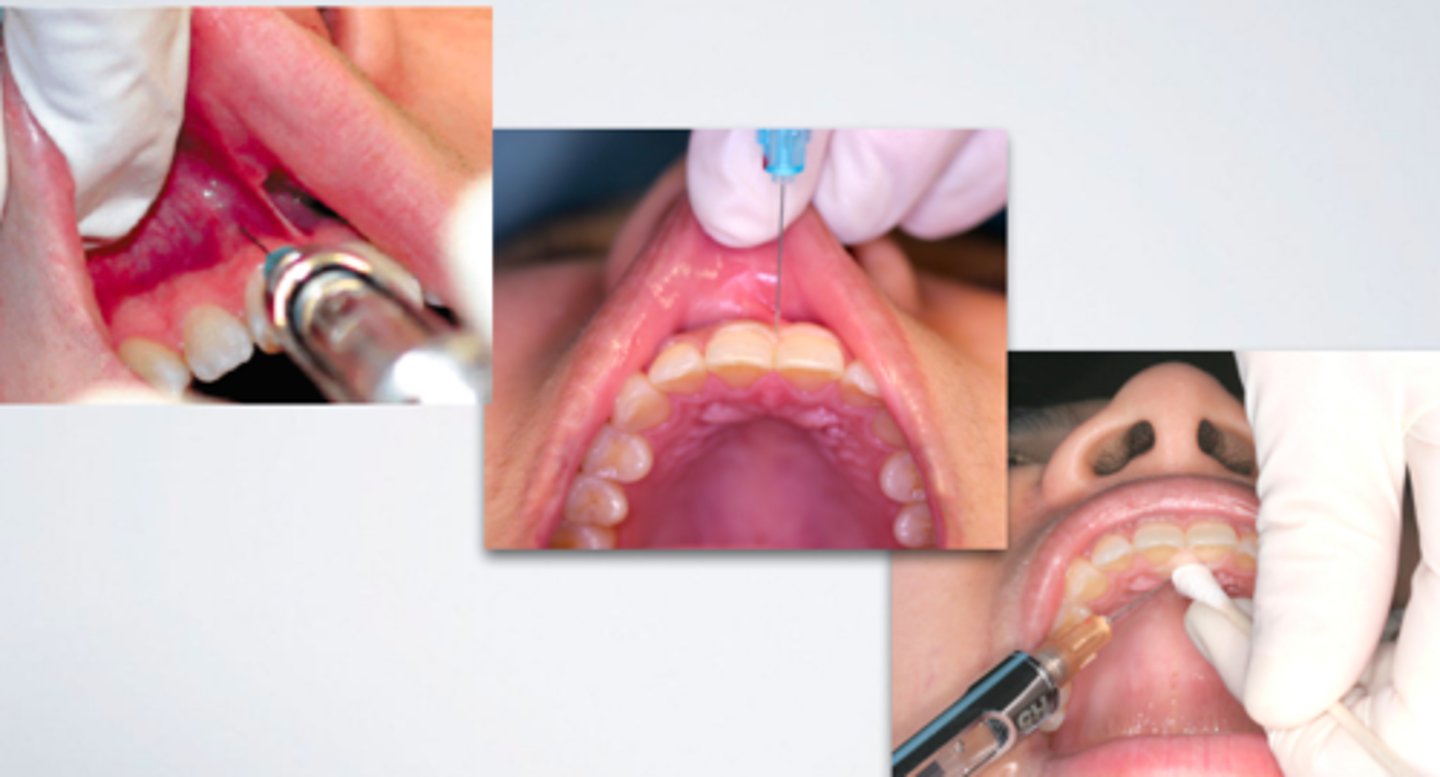

palatal injections

What type of injection can be the most painful for a patient to experience?

-Use pressure anesthesia at the injection site before and during needle insertion

-Deposit the anesthetic solution slowly

What are 2 ways to reduce the amount of pain experienced by patients during a palatal injection?

Greater Palatine Nerve Block

ID the anesthesia technique:

Nasopalatine Nerve Block (single injection)

Nasopalatine Nerve Block (multiple injections) #2

Palatal Local Infiltration

High Tuberosity Approach (for maxillary nerve block)

Pterygopalatine/Greater Palatine Canal Approach (for maxillary nerve block)